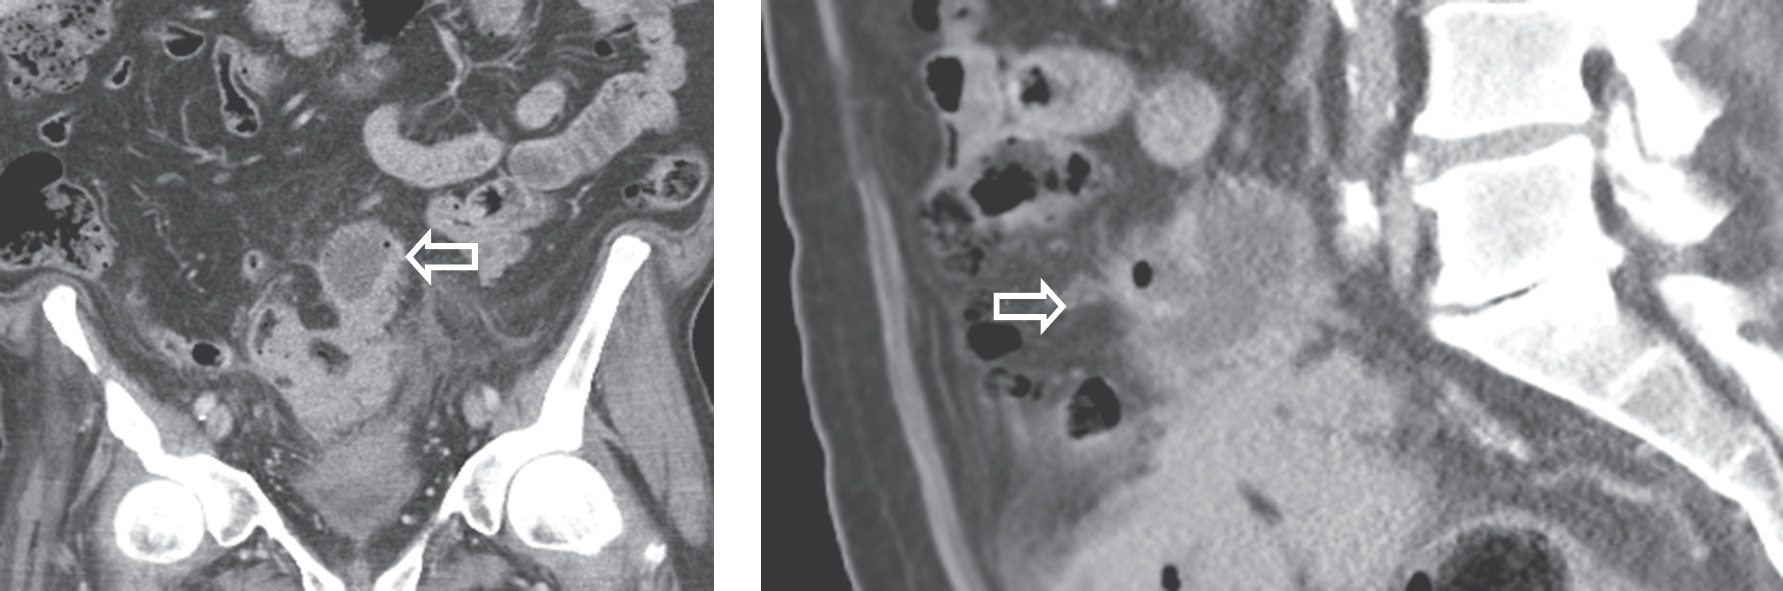

Всем больным в обязательном порядке в течение двух часов от момента поступления проводили обследования в минимальном объеме, включавшие обзорную рентгенографию живота и грудной клети, ЭКГ, УЗИ органов брюшной полости и почек, клинический анализ крови, биохимический анализ крови, общий анализ мочи, осмотр терапевта. При рентгенографии живота, как правило, наблюдался пневматоз толстой кишки, реже пневматоз тонкой кишки. Рентгенологическая картина менялась при развитии распространенного перитонита — появлялись тонко- и толстокишечные уровни, кишечные арки. Ультразвуковое исследование играло вспомогательную роль в постановке правильного диагноза с определением тактики дальнейшего лечения. Параколярный инфильтрат в виде местного уплотнения ткани в проекции предполагаемой опухоли по данным УЗИ был выявлен у 16 (65,5 %) больных (рис. 2).

Рис. 2. Опухоль восходящей ободочной кишки с перифокальным воспалением

Fig. 2. Ascending colon tumor with perifocal inflammation

Отграниченное скопление жидкости в области инфильтрата визуализировано у 3 (5,5 %) пациентов, свободная жидкость в брюшной полости обнаружена у 2 (3,6 %) больных. Кроме того, УЗИ позволяло выявить метастатическое поражение печени, стадировать процесс, что в некоторой степени также влияло на тактику ведения пациентов. Существенную роль в выявлении перифокального воспаления при отсутствии клинической картины играла спиральная компьютерная томография. Утолщение стенки кишки с неравномерным, достаточно часто циркулярным сужением просвета в сочетании с тяжистостью, уплотнением окружающей ткани позволяли достаточно достоверно диагностировать ПФВ. Появление газа в параколярной клетчатке свидетельствовало о формировании параканкрозного абсцесса или перфорации опухоли (рис. 3).